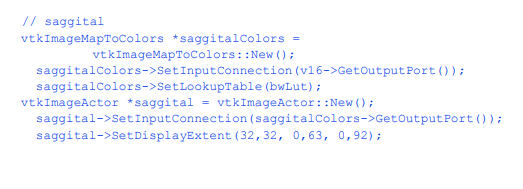

我们将提取三个正交平面,对应于放射科医生熟悉的轴向、矢状和冠状截面。轴向面垂直于患者颈部,矢状面从左到右,冠状面从前到后。为了便于说明,我们使用不同颜色的查找表来呈现每个平面。对于矢状面,我们使用灰度。冠状面和轴向面分别改变饱和度和色相表。我们将其与皮肤的半透明渲染相结合(我们使用c++语句bone- >VisibilityOff()关闭骨骼)。下面的VTK代码创建了纹理映射过程中使用的三个查找表。

使用筛选器vtkImageMapToColors结合上面创建的查找表将图像数据映射到颜色。切片的实际显示是使用vtkImageActor执行的(有关更多信息,请参阅第74页的“程序集和其他类型的vtkProp”)。这个类方便地将一个四边形、多边形平面与纹理映射结合在一起。vtkImageActor需要unsigned char类型的图像数据,类vtkImageMapToColors方便地提供了这种数据。为了避免复制数据并指定要使用的2D纹理,需要适当地设置每个vtkImageActor的DisplayExtent。c++代码如下:

合成图像如图12 - 4所示。在本例中,名为skin的参与者最后呈现,因为我们使用的是半透明表面。回想一下第213页的“透明度和Alpha值”,我们必须对多边形进行排序,图12-4三个平面和半透明皮肤的合成图像(Medical3。cxx)。12.2从分段的卷数据445中创建模型,组合透明表面以获得正确的结果。我们最后渲染皮肤,将其添加到aRenderer的演员列表中。